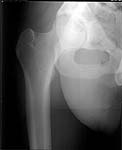

22 yrs man , semiprofessional( he earn some money from playing) basketball player got suffered in car accident.He had hip joint posterior luxation ( Pipkin 4) with little acetabular roof fragments ( nondisplaced) and anterosuperior abruption fracture of the head of the femur.

Additional injuries were severe face wounds. Emergency manipulations were reposition of the hip luxation under the radiologic control and wounds care. After reposition the CT scan was made. We found 2x3cm wide and 0.5 thick OCH fragment outside the joint surfaces , under the caput. The traction was applied.

I don't know what chance ORIF has of working. I'm not sure you can get the piece to heal very well. It's markedly displaced, almost certainly avascular. It looks pretty thin.

Since the defect location is cephalad/anterior, and the fragment is caudal to the head anteriorly, you'll need an anterior surgical exposure...if you select a posterior exposure, you may be "comfortable"...but you'll be "sad" then "mad", since you won't see the defect. (see below)

Here are the missing postreduction views.